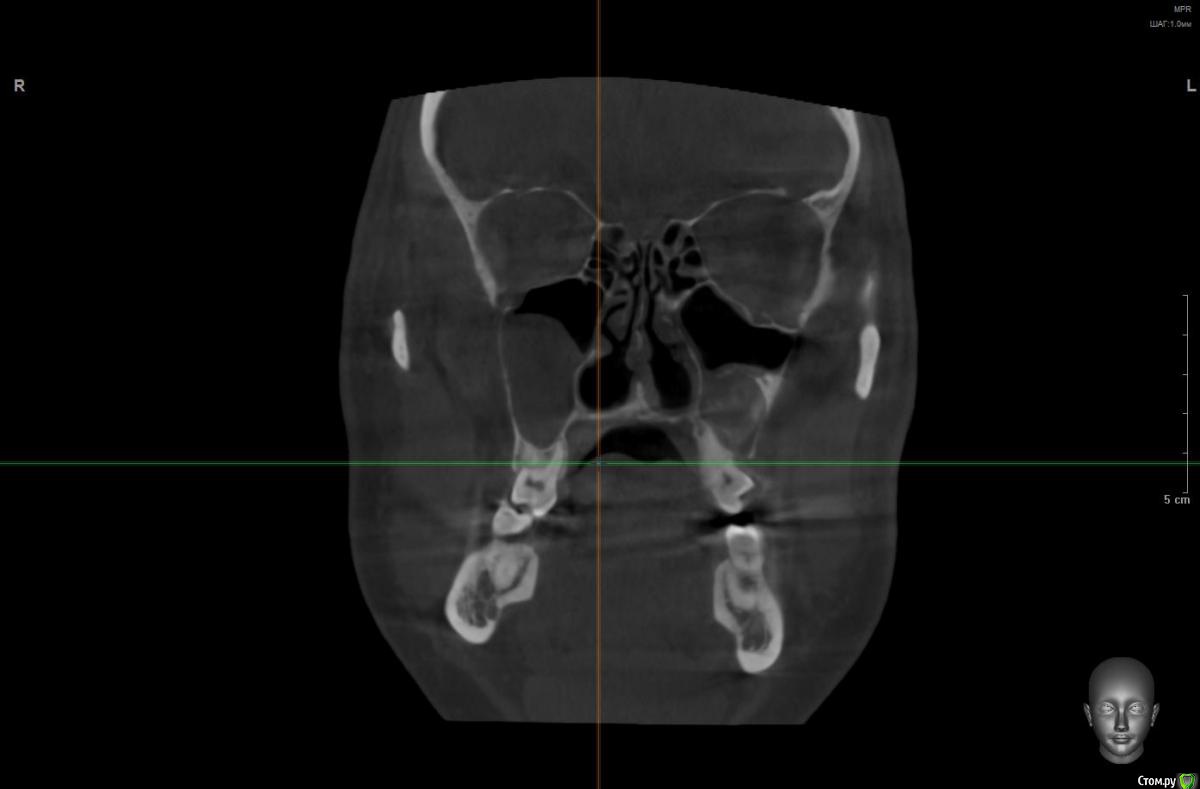

wladdX Опубликовано 5 марта, 2019 Поделиться Опубликовано 5 марта, 2019 Корональная проекция Сагиттальная справа Сагиттальная слева 16 26 28 Ссылка на комментарий

kramer Опубликовано 5 марта, 2019 Поделиться Опубликовано 5 марта, 2019 В общем скачал я КТ. Что касается зуба 26, да, там есть признаки воспаления вокруг корней, лечить / удалять зависит от состояния тканей зуба и возможностей врача. Но лично мне не кажется, что этот зуб играет главную роль в возникшем гайморите. Обратите внимание, в области 8 зуба (см. срез) внутри пазухи есть некий очаг, содержащий неоднородные по плотности элементы (более светлые включения, а выше пузырьки воздуха). Снимок не особо четкий, но такое ощущение, что в области 8 зуба вообще нарушена целостность боковой стенки пазухи. Кроме того, с правой стороны все зубы в порядке, а явления гайморита тоже имеются (там вообще почти вся пазуха забита). Соустья с носом закрыты. В общем, в данной ситуации я бы более детально обследовал 8 зуб, если там все нормально, то пусть ЛОРы эндоскопически лезут в пазухи и убирают это все. Ссылка на комментарий